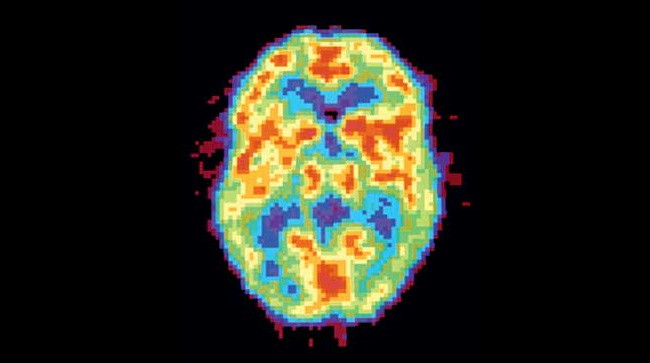

Активность мозга сильно различается не только во время бодрствования и сна — есть множество промежуточных состояний, которые можно различить во время позитронно-эмиссионной томографии.